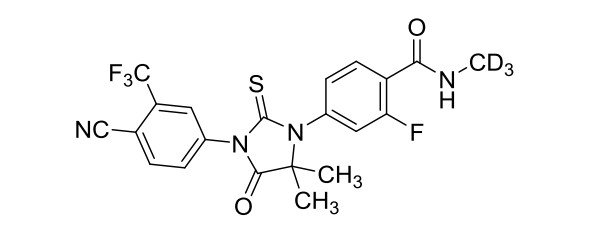

化学名称:4-[3-[4-氰基-3-(三氟甲基)苯基]-5,5-二甲基-4-氧代-2-硫代-1-咪唑烷基]-2-氟-N-三氘代甲基苯酰胺

化学结构式:

分子式:C??H??D?F?N?O?S

分子量:467.45